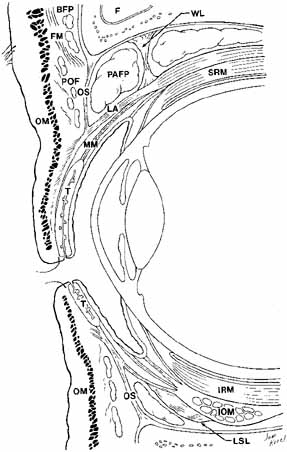

above the superior tarsal border in non-Asians11 (see Fig. 8). In Asian lids, the orbital septum fuses to the levator aponeurosis

at a level below the superior tarsus, allowing preaponeurotic fat

to prolapse inferior and anterior to tarsus; in the lower lid, it may

fuse directly to the inferior tarsal border rather than joining with the

retractors. An absent or lower lid crease in Asian eyelids may be due

to this fat protrusion and other subcutaneous fat tissue that inhibits

levator fibers from inserting into the subdermal skin.12  Fig. 8 Parasagittal section to show anterior orbital structures. (F, frontal sinus; SRM, superior rectus muscle; FM, frontalis muscle; MM, Müller's muscle; BFP, brow fat-pad; T, tarsus: POF, postorbicularis fascia; OM, orbicularis muscle; OS, orbital septum; LSL, Lockwood's suspensory ligament; PAFP, preaponeurotic fat-pad; IOM, inferior oblique muscle; WL, Whitnall's ligament; IRM, inferior rectus muscle; LA, levator aponeurosis) Fig. 8 Parasagittal section to show anterior orbital structures. (F, frontal sinus; SRM, superior rectus muscle; FM, frontalis muscle; MM, Müller's muscle; BFP, brow fat-pad; T, tarsus: POF, postorbicularis fascia; OM, orbicularis muscle; OS, orbital septum; LSL, Lockwood's suspensory ligament; PAFP, preaponeurotic fat-pad; IOM, inferior oblique muscle; WL, Whitnall's ligament; IRM, inferior rectus muscle; LA, levator aponeurosis)

The septum may attenuate with age allowing orbital fat to herniate forward, requiring

blepharoplasty. In performing levator surgery or blepharoplasty

the preaponeurotic fat is encountered just posterior to the septum. Loose

areolar tissue, termed the suborbicularis fascia, lies immediately anterior to the septum13 and shares the same plane as the eyebrow retro-orbicularis oculi